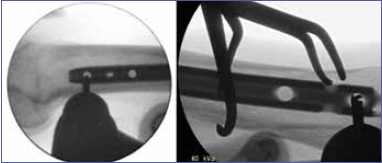

We have been utilizing a very simple technique to aid locate the screw holes positions for femoral, tibial and humeral interlocking nails, employing a commonly available instrument in the operating room, which we feel is both easy and reliable while attempting to limit the amount of radiation exposure. Crucial preparation for successful placement includes the utilization of the image intensifier. Once the intramedullary nail has been successfully inserted, a lateral fluoroscopic view of the end of the nail is obtained. The limb has to be placed over a bump to be elevated compared to the contralateral and to obtain an unobstructed view. The position of the image intensifier C arm needs to be adjusted until the screw holes are visualized as “perfect circles” (Fig. 1). At times, even the limb must be rotated or ab-adducted to obtain the best view in the lateral projection. We stress the opportunity of having the monitor in front of the surgeon, with the limb in the same direction as it is in the video. We then utilize a simple open tonsil forceps, with the ratchet serving as a reference point, on the surface of the skin. (Fig. 2A-B). The oval of the forceps hand is centered on the distal hole of the nail and the ratchet will show the accuracy of the position, complementary of the C arm (Fig. 2C). A minimum of X-rays is necessary at this point, since the oval of the instrument provide a good reference position for the holes in the nail. At this point a stab incision is performed, from skin to periosteum, in line with the screw hole in the nail (Fig. 3A-B).Once the perfect circles have been rechecked and confirmed, a drill is positioned on the circle’s image, with the drill tip lined up on the superior aspect of the hole, aiming from superior to inferior (Fig. 4). Initially, slow drilling is paramount to successfully start the opening of the cortex. Subsequentially, the same maneuver must be repeated from below up. (Fig. 5A-B). In this way the hand of the operator will not prevent the visualization of radiographic images. The drill is passed through the near side cortical bone, near the screw hole, far screw hole and then far side cortical bone (Fig. 6A-B). The same steps are repeated for the second hole, always maintaining a drill bit in one hole while drilling the second one, as to not lose the position with the locking screws holes. The image intensifier C arm is then rotated through 90° to obtain an anteroposterior projection, so that one can measure the length of the screws and insert them (Fig. 7A-D).

Figure 6.A-B) Drill bit drilling outer and inner cortex for insertion of distal locking screws.

Figure 7.A-B) Measurement of the length of the drill inside the bone for the corresponding screw.